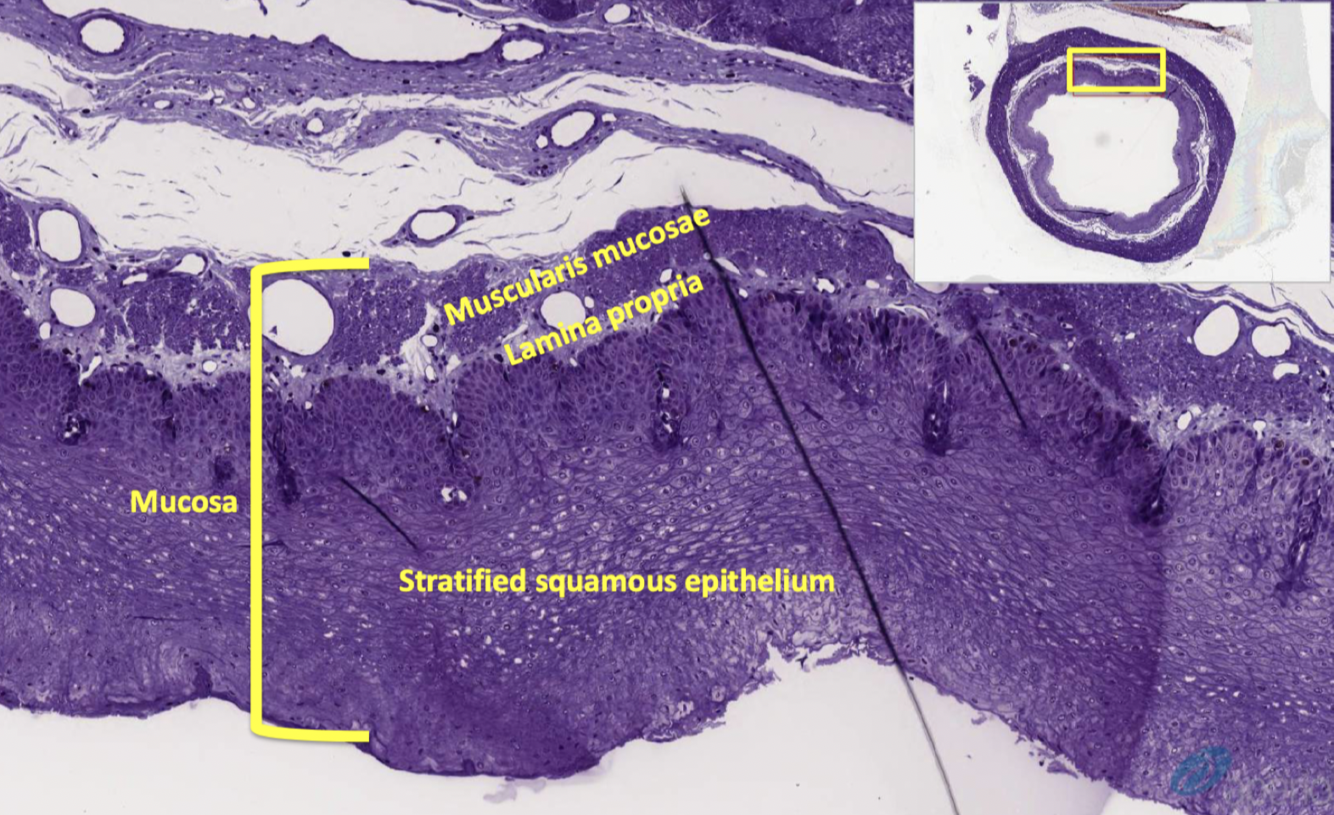

mucosa composed of

muscularis mucosae

what is lamina propria

what is muscularis mucosae

organization of tissue layers of GI tract